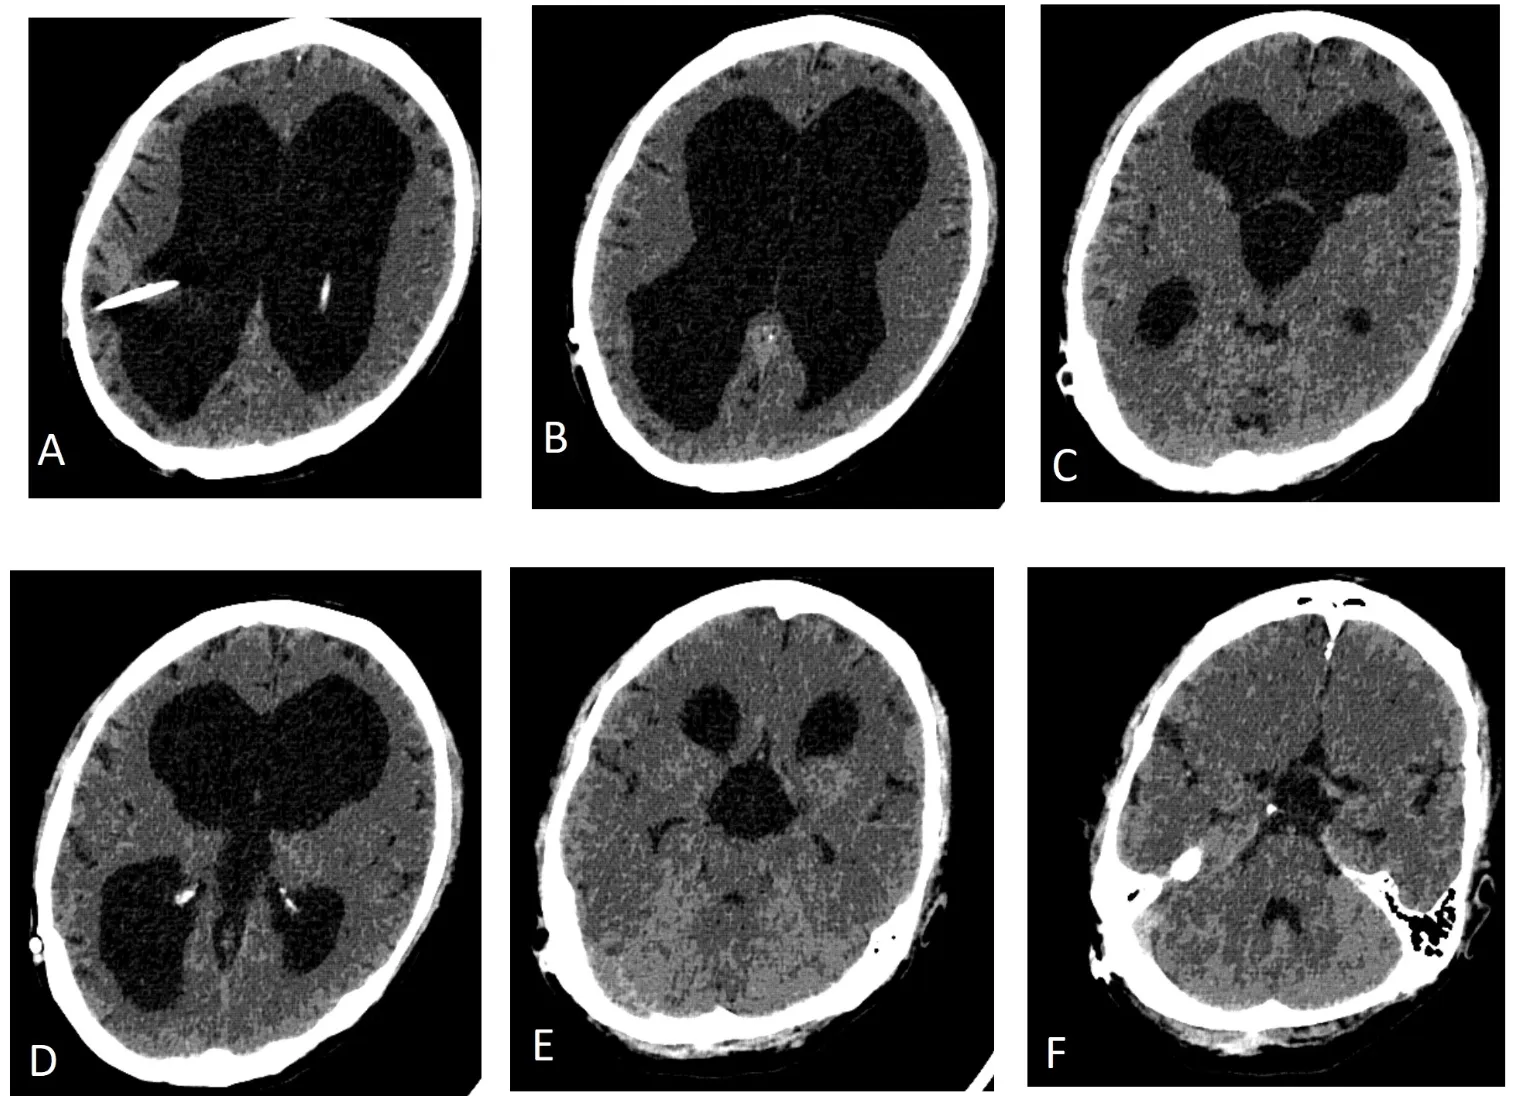

CT scan of head showed triventricular hydrocephalus with intact 4th ventricle, with widely patent foramen of Monro bilaterally. However, there was a slight hyperdensity of third ventricular CSF raising suspicion of a sequestered third ventricle, compared to CSF density in the lateral ventricles. Since there were no CT scans prior to this admission available for comparison, a CT ventriculogram was planned.

CT ventriculogram demonstrated a trapped third ventricle secondary to bilateral foramen of Monro obstruction or occlusion, with intact fourth ventricle. Figure 1 shows cranial CT with triventricular hydrocephalus and right VP shunt. The contrast dye placed in the frontal horn of lateral ventricle was not seen entering the third ventricle at all, even on follow up scans shown in Figures 2 and 3. No contrast egress was noted into the rounded enlarged third ventricle. Eventually the dye cleared off the lateral ventricles as demonstrated in Figure 4 done 24 hours after contrast injection. Given the fact that the patient improved neurologically and there was a possibility of arrested hydrocephalus, he was started on a higher dose of Keppra and he was discharged home at his neurologic baseline exam.